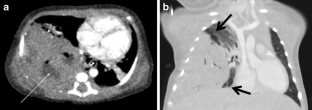

Fig. 2